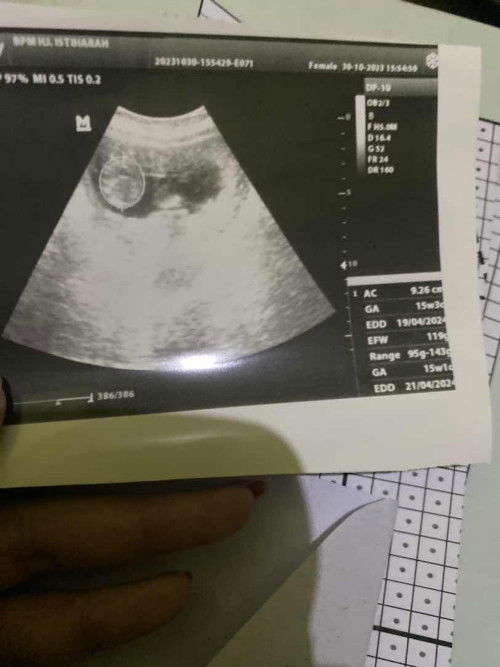

Hasil ug 2d usia janin 15W

Tidak terlalu kelihatan ya bun pas udah dicetak tapi alhamdulillah semua nya bagus kada bidan nya perkembangan sesuai umur dan berat janin 119gr

Usia janin 15 week

Apakah sudah kelihatan jenis kelamin nya ya kalo USG yg 2D usia janin 15w